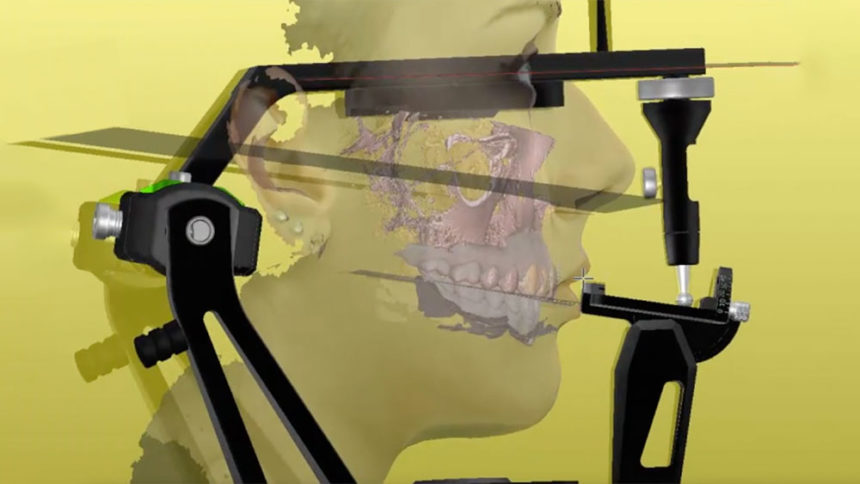

Restorative strategies in tooth-supported rehabilitations - Speaker: Giacomo Fabbri

- Classification of all-porcelain materials

- The full-mouth mock-up: a dynamic diagnostic approach (DDA) to test function and esthetics in complex rehabilitations

- Increasing the vertical dimension of occlusion: when, why and how.

- Biomechanical end esthetic properties

- What is it necessary to know about the occlusion

- Layered and Monolithic approach: advantages and drawbacks

- The role of the adhesion in the prosthetic therapy

- Minimal invasive approach and new trends on teeth preparations

- New trends on management the temporary restorations

- Guide lines on selection and management the final restorative materials

- Final restoration: try-in and cementation

- Tip and tricks for the daily practice